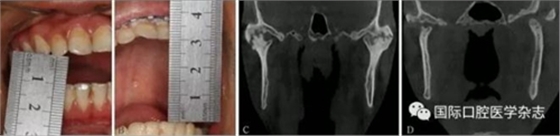

A:術(shù)前開口度;B:術(shù)后開口度;C:術(shù)前影像學(xué)檢查片;D:術(shù)后影像學(xué)檢查片。

圖 18 關(guān)節(jié)盤復(fù)位錨固術(shù)前后對(duì)比

圖 19 關(guān)節(jié)成形術(shù)前后對(duì)比